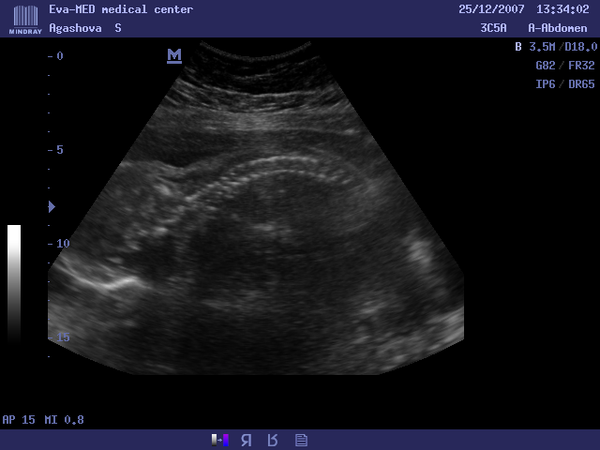

Нашла диск с фото с узи на 24 недели(25.12.2007г.),так трогательно,аж слезы текут рекой.Тогда нам сказали что у нас будет девочка,а родился мальчик)))